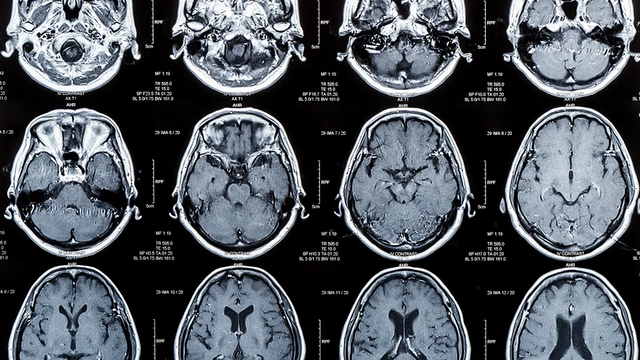

뇌 CT

인간의 뇌는 노화로 인해 다양한 변화를 겪는다